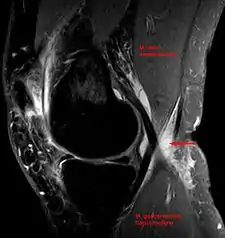

In adults, Baker's cysts usually arise from almost any form of knee arthritis (e.g., rheumatoid arthritis) or cartilage (particularly a meniscus) tear. Baker's cysts in children do not point to underlying joint disease. Baker's cysts arise between the tendons of the medial head of the gastrocnemius and the semimembranosus muscles. They are posterior to the medial femoral condyle.

Baker's cyst on MRI, sagittal image